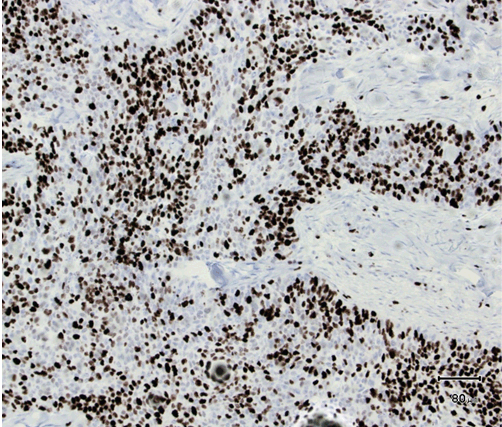

A 61-year-old male was presented to his dermatologist with a solitary nodular dermal lesion on his lower back (1.5x2 cm). He was otherwise well and was taking no medication. A biopsy demonstrated squamous cell carcinoma (SCC), and the patient was referred to our service for complete local excision. On follow-up, a month later, the patient presented with hemoptysis, hip-, and abdominal pain. Magnetic resonance imaging (MRI) scan confirmed the presence of lung, liver, and bone multiple metastases. As planned, a complete local excision with a 7.5 mm margin was performed. Histology confirmed the diagnosis of SCC. Furthermore, the patient had developed another solitary dermal lesion localized to the chin. This lesion was not present only a month prior during the visit to the dermatologist. A biopsy from this lesion also demonstrated SCC. The specimens from the back and chin were later studied with immunohistochemistry. The morphology suggested SC, with the tumor showing a solid arrangement of cells with nuclear pleomorphism, atypical mitosis, basophilic and vacuolated cytoplasm (Figure 1) and (Figure 2). In addition, immunohistochemistry showed tumor positive for epithelial marker Ber-EP4, pancytokeratin (Kl1) and epithelial membrane antigen (EMA) (Figure 3). Reactivity for p53 and proliferating cell nuclear antigen (Ki67) was high, showing 80–90% hot spots labeling of the tumor cells (Figure 4) and (Figure 5). Immunoreactivity levels of cancer protein p53 and Ki67 above 10 and 25% indicated a poor prognosis (Figure 6). It was then concluded that the correct diagnosis of both tumors was in fact SC and not SCC.

Figure 4: Hot spots for P53 (H&E stain, x100).